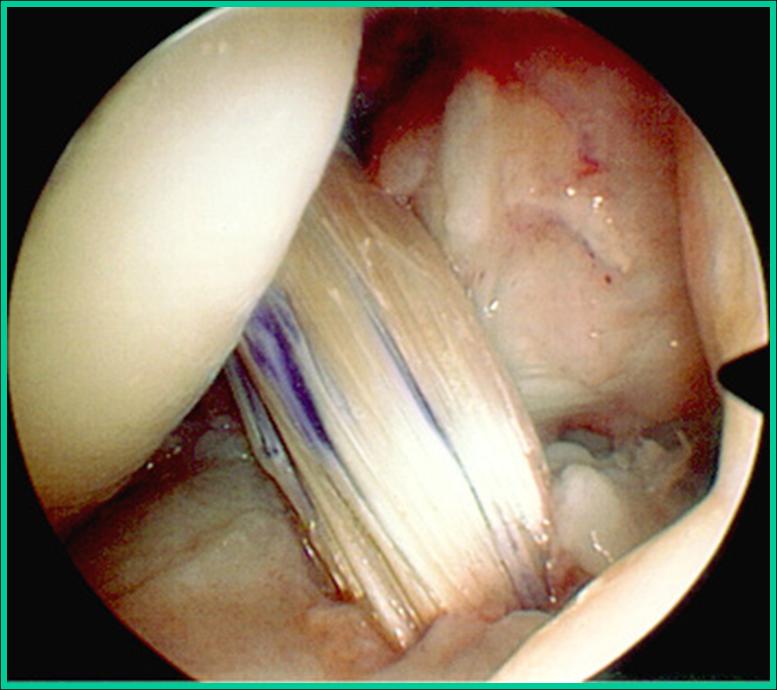

Η θεραπεία της ρήξης των μηνίσκων είναι συνήθως χειρουργική με αρθροσκόπηση. Κατά την διάρκεια του χειρουργείου ο χειρουργός αφαιρεί το σπασμένο (ρηχθέν) τμήμα του μηνίσκου (αυτή είναι η συνηθέστερη πρακτική) ή όταν οι συνθήκες το επιτρέπουν προχωρά σε συρραφή του μηνίσκου.

- Arthroscopic meniscal repair.